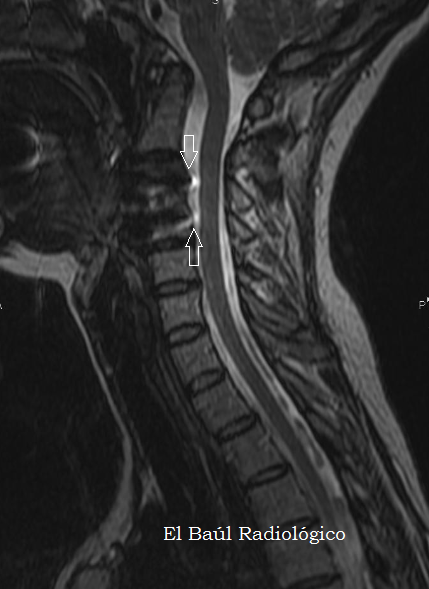

FIGURA 4) Secuencia FSE-T1. La placa metálica de titanio produce artefactos de susceptibilidad magnética (flechas) que impiden la correcta visualización de los cuerpos vertebrales en los que está insertada, pero no dificultan la exploración de la médula y el canal espinal.

(FSE-T1 MRI Sequence. The titanium metal plate produces magnetic susceptibility artifacts (arrows) that prevent the correct visualization of the vertebral bodies in which it is inserted, but does not difficult the exploration of the cord and the spinal canal).